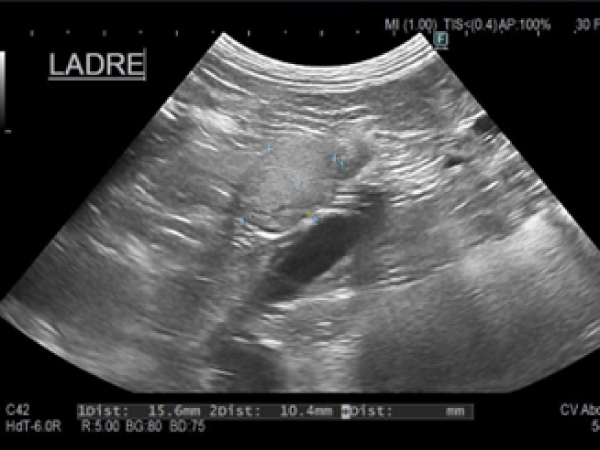

定期検診の時に、右側副腎の腫大を見つけました。

↑実際に取り出した右副腎 (1.7×1.8cm)

犬の右副腎2.5cm。腹腔鏡下手術。3ポートで摘出が可能。